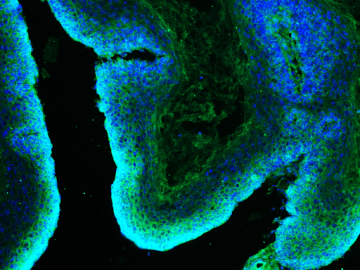

Building on this work, Carlos Galván, a graduate student in Lowry’s lab and the new study’s first author, has been investigating the extent of this metabolic flexibility and whether it could be curtailed. Working with mouse models, he genetically blocked the pathway glutamine uses to fuel cells in hair follicle stem cells — a known cell type of origin for squamous cell skin cancer — and observed its effect on the formation and growth of tumors. As with the previous experiments, the tumors simply switched to another nutrient source.

Next, the researchers tried what they call a “double hammer” approach: genetically blocking the pathways for both glucose and glutamine metabolism by deleting the transmitter that allows uptake of respective enzymes. This dual-target strategy was enough to prevent the cancer from growing in mouse models.